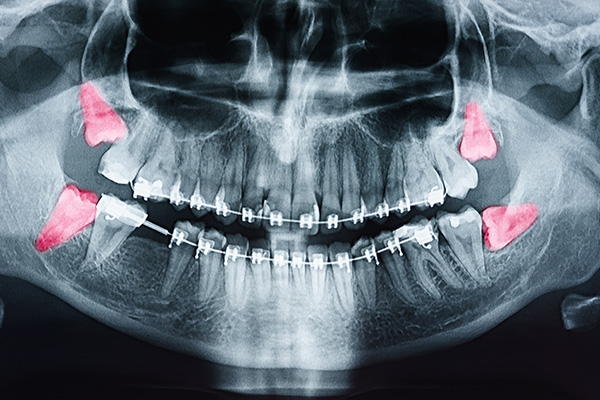

A careful diagnosis starts with a thorough medical and dental history followed by a focused intraoral exam. We routinely use panoramic radiographs to view all third molars and their relationship to the jaw, and we employ 3D imaging when finer detail is needed. Three-dimensional x-rays provide precise information about root configuration, bone density, and proximity to critical structures such as the inferior alveolar nerve or the maxillary sinus.

Evaluation begins with a thorough medical and dental history and a focused intraoral examination to assess eruption, gum health, and signs of infection or decay. Panoramic radiographs are routinely used to view all third molars and their relationship to surrounding structures, and three‑dimensional imaging may be employed when more detail is required. Imaging reveals root shape, bone density, and proximity to critical anatomy such as the inferior alveolar nerve or the maxillary sinus.